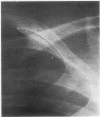

The thickness of the shadows that accompany ribs or border the lungs on the chest postero-anterior radiographs of 22 obese patients and 22 normal-weight subjects was measured, when present, at several rib levels. A similar measurement was made of accompanying rib shadows on chest postero-anterior radiographs of eight obese patients after weight reduction. Statistical analysis showed that there were significantly thicker soft tissue shadows adjacent to the ribs of obese subjects compared to normal-weight persons and of obese subjects before as compared to after weight reduction. Such shadows are more frequent and are seen at more rib levels of the obese.